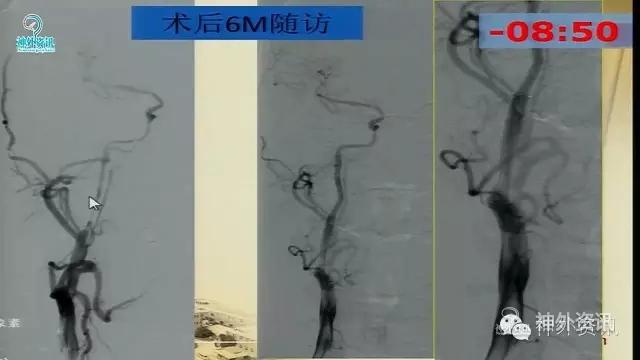

万杰清教授:慢性颈动脉闭塞再通技术及临床效果